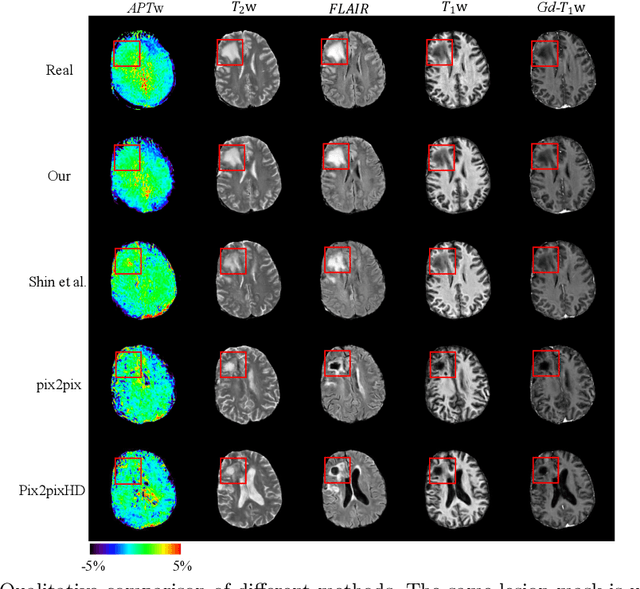

Abstract:Data-driven automatic approaches have demonstrated their great potential in resolving various clinical diagnostic dilemmas for patients with malignant gliomas in neuro-oncology with the help of conventional and advanced molecular MR images. However, the lack of sufficient annotated MRI data has vastly impeded the development of such automatic methods. Conventional data augmentation approaches, including flipping, scaling, rotation, and distortion are not capable of generating data with diverse image content. In this paper, we propose a generative adversarial network (GAN), which can simultaneously synthesize data from arbitrary manipulated lesion information on multiple anatomic and molecular MRI sequences, including T1-weighted (T1w), gadolinium enhanced T1w (Gd-T1w), T2-weighted (T2w), fluid-attenuated inversion recovery (FLAIR), and amide proton transfer-weighted (APTw). The proposed framework consists of a stretch-out up-sampling module, a brain atlas encoder, a segmentation consistency module, and multi-scale labelwise discriminators. Extensive experiments on real clinical data demonstrate that the proposed model can perform significantly better than the state-of-the-art synthesis methods.